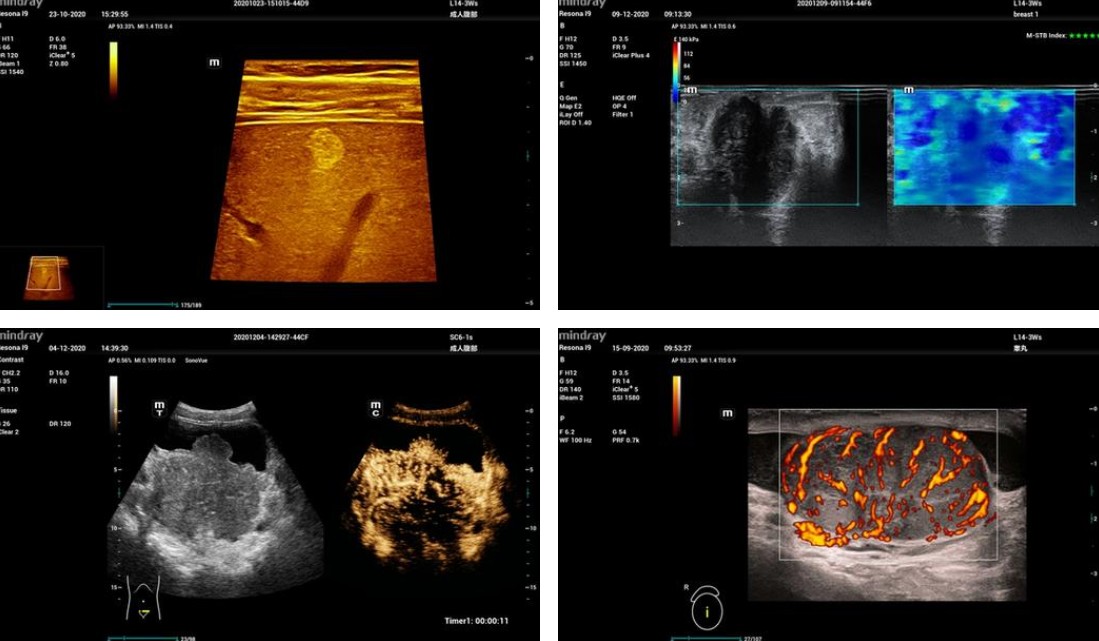

#Mindray's Resona I9 is a high-end ultrasound system designed to deliver an unrivalled diagnostic experience. Featuring the innovative ZST+ platform, it combines exceptional image quality, state-of-the-art ergonomics and remarkable clinical intelligence. With its accurate analysis tools, intelligent features such as Smart Breast and Smart Thyroid, and its foldable, quiet design, it adapts to all clinical environments. It offers unprecedented flexibility and increased productivity, ensuring reliable diagnosis and optimal patient care.

This system features an extensive suite of artificial intelligence (AI)-enhanced technologies, which improve reproducibility, optimize productivity, and increase consistency for end-users. The enriched Glazing Flow technology provides optimal visualization of micro-vascular perfusion states, while the Contrast-Enhanced Ultrasound (CEUS) imaging improves contrast and temporal resolution during CEUS studies. The Sound Speed Compensation (SSC) algorithm automatically detects and analyzes different tissue characteristics to determine the optimal signal speed needed for improved image quality. The system's Shear Wave Elastography (SWE) allows for smoother transition times and faster refresh rates, ensuring more consistent acquisition and assessment during live 2D shear wave imaging.